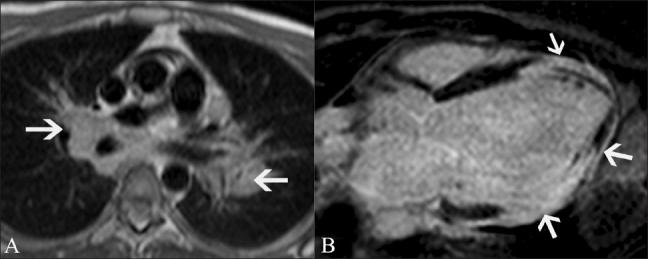

磁共振成像在评估心电图ST段抬高患者中的应用价值。

Utility of magnetic resonance imaging in the evaluation of patients with ST segment elevation on an electrocardiogram.

ST segment elevation is an important electrocardiographic (ECG) change that is typically found in acute myocardial infarction, but may also be seen in a variety of other conditions. MRI plays an important role in the evaluation of these patients. MRI not only establishes the diagnosis, which is essential for appropriate management, but also helps in the assessment of other factors that are important for risk stratification. In this review, we discuss the common and uncommon causes of ST segment elevation and the role of MRI in the evaluation of these disease processes.

摘要